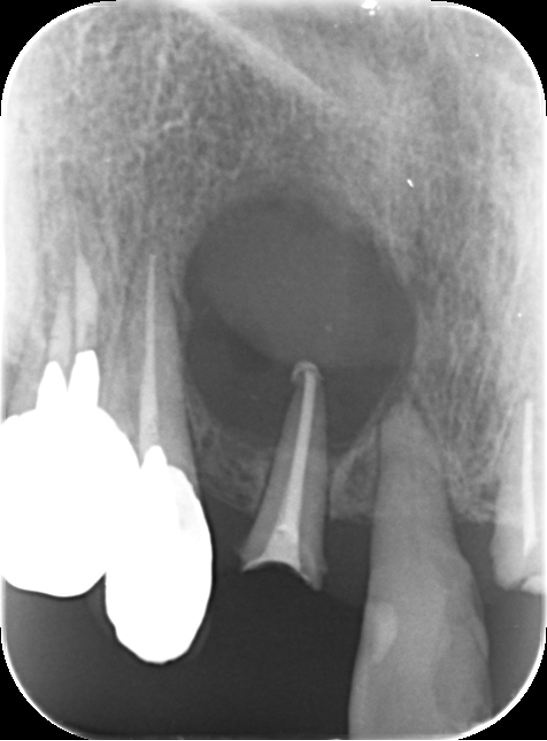

6ヶ月後のレントゲン(右側)を術前のレントゲン(左側)を比較します。かなり改善され骨が新生しています。順調です。